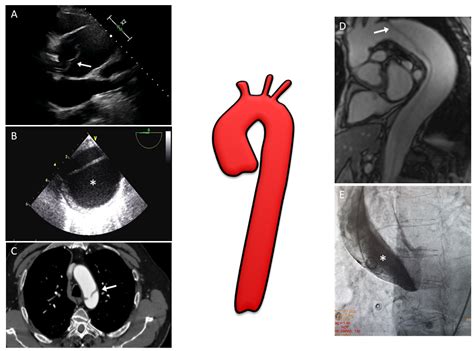

How Doctors Diagnose Ectasia

Because symptoms are often absent, imaging is the gold standard for diagnosing and tracking the progression of aortic dilation. Physicians rely on several non-invasive tests to evaluate the size and shape of the aorta:

Diagnostic Test Purpose

Echocardiogram Uses sound waves to visualize the heart and the base of the aorta.

CT Angiography Provides high-resolution 3D images of the aorta to measure exact dimensions.

Magnetic Resonance Angiography (MRA) Offers detailed imaging without the use of ionizing radiation.